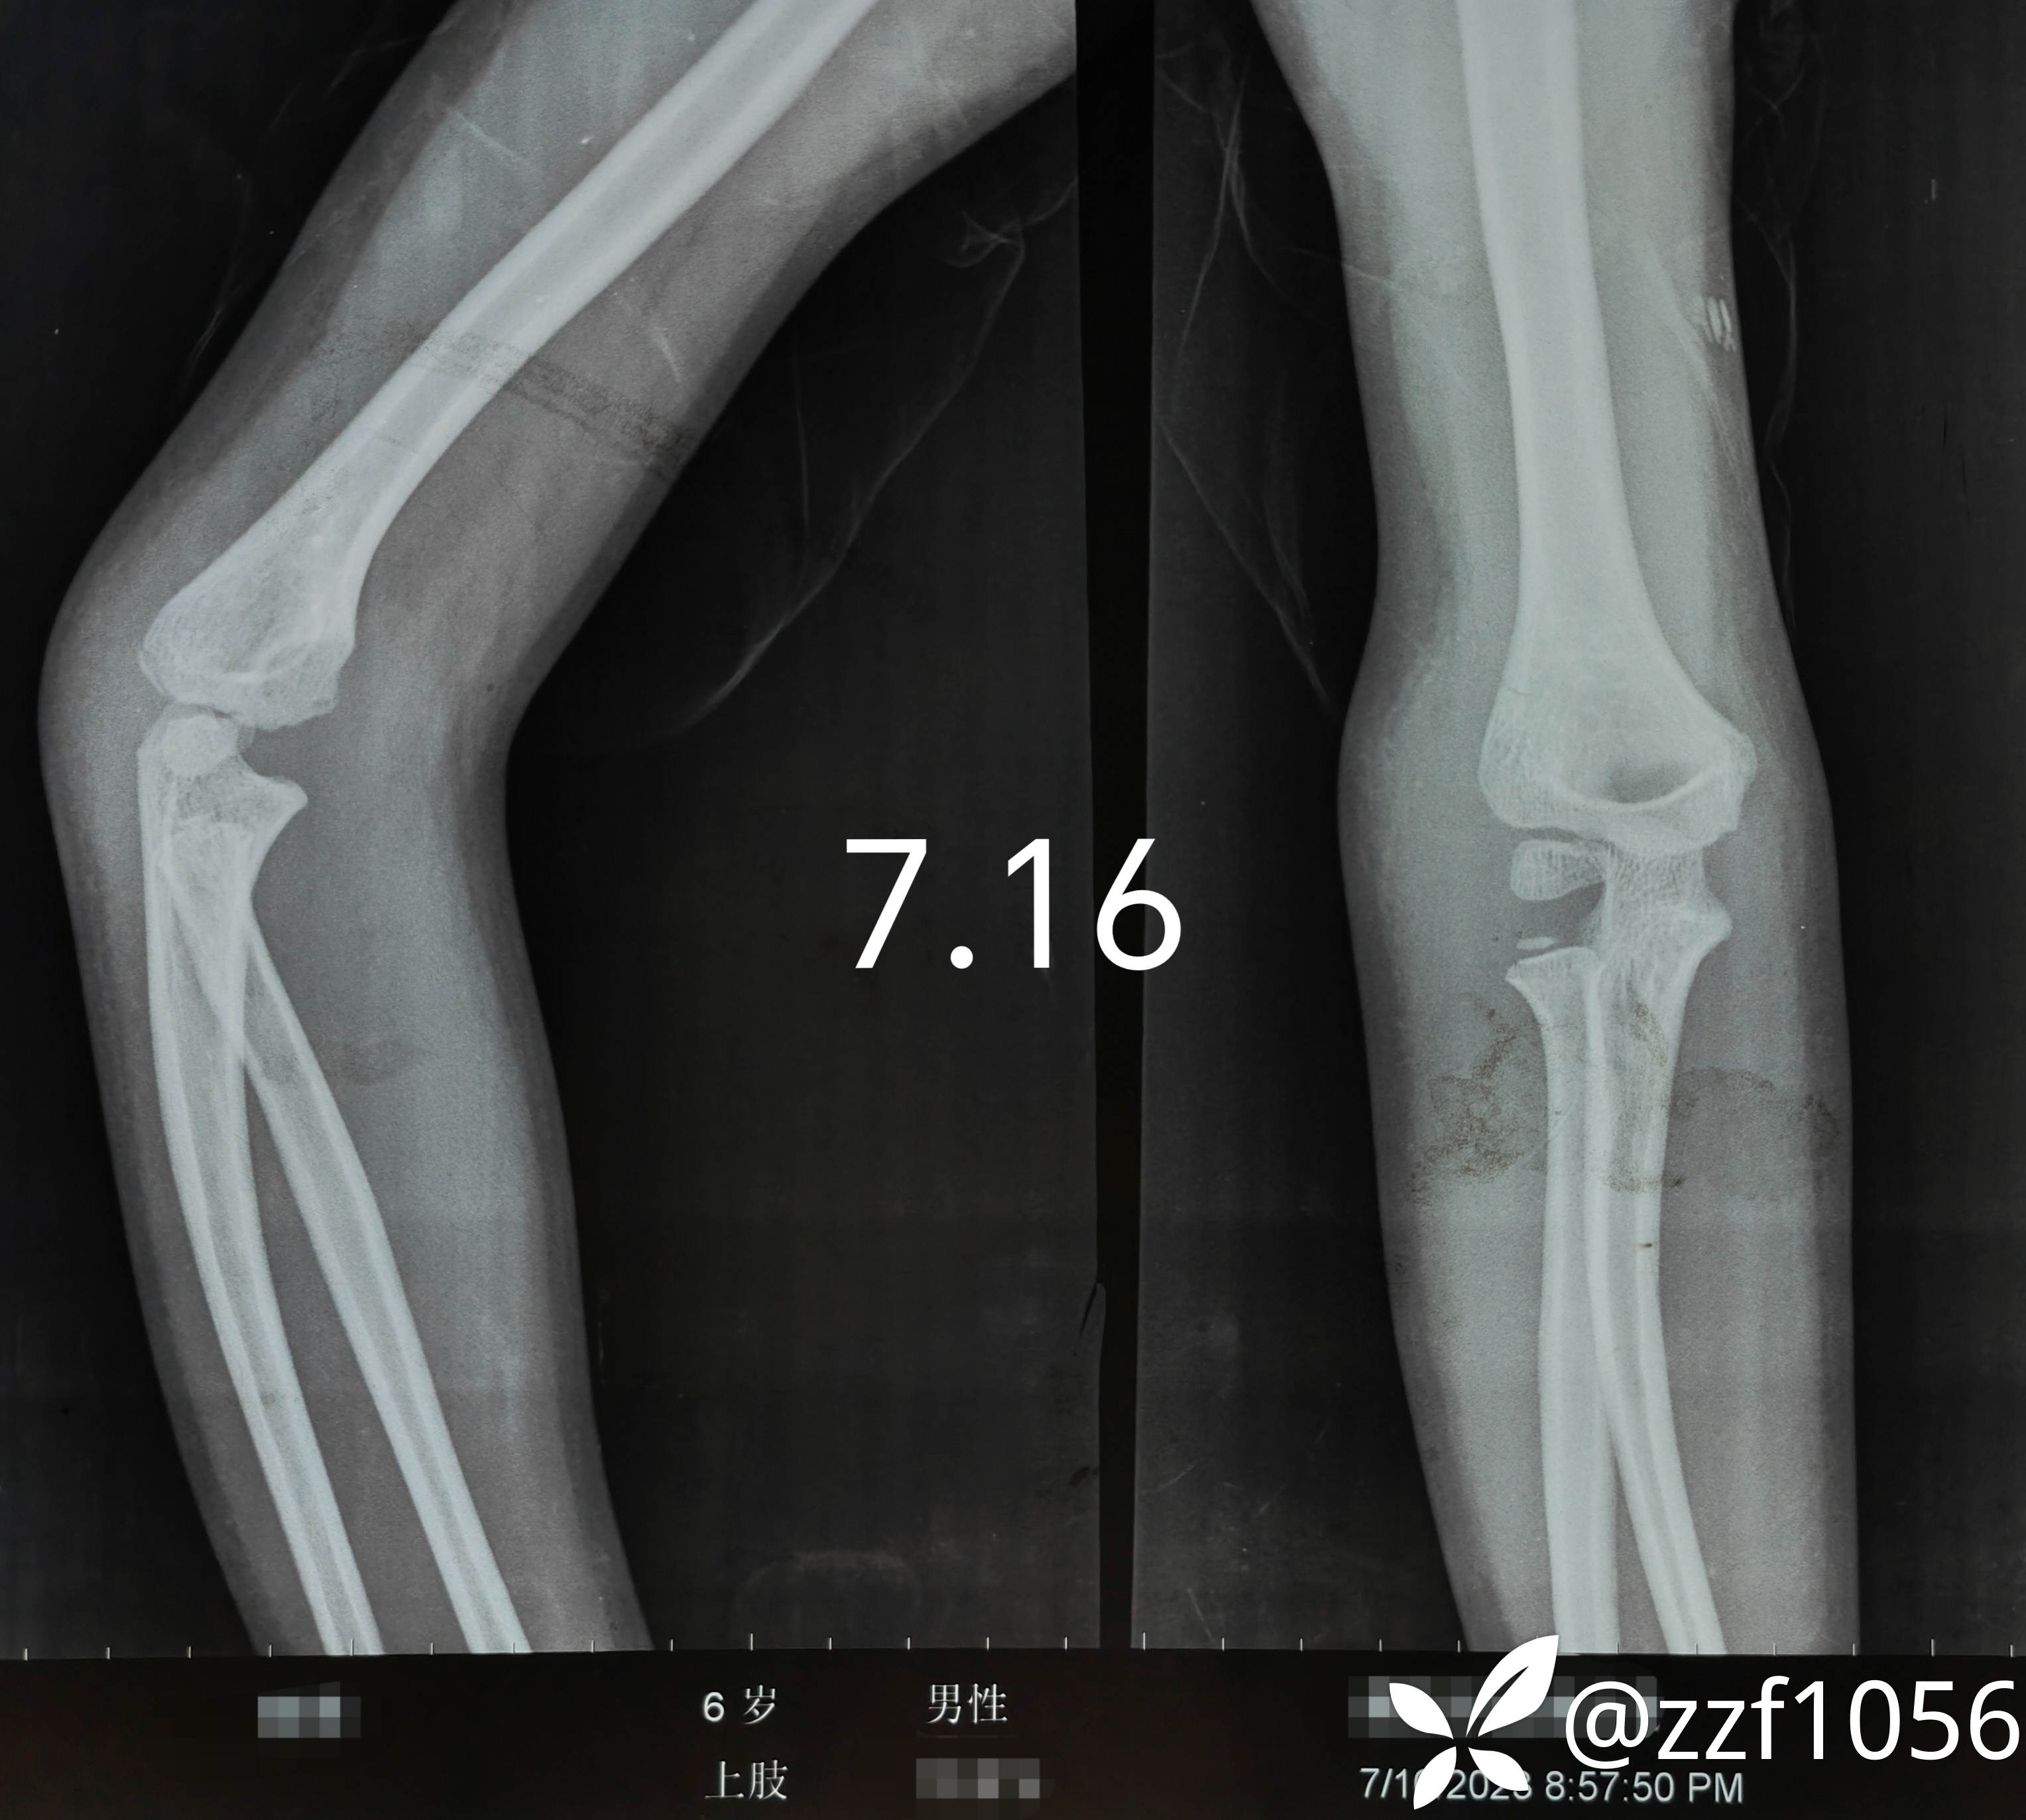

【病例讨论】儿童肱骨外髁陈旧骨折(外伤一月),继续保守还是手术?

患者男性,6岁,摔伤右肘疼痛一月。

受伤后赴当地医院拍片

家属诉当时大夫告知未见骨折,贴了膏药回家修养

休息半月患者肘部仍疼痛,带来我院门诊复查

当时门诊大夫打了个石膏保守治疗